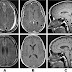

Eastchester Clapping sign

Hand clapping is a motor program mastered in infancy. A patients with hemispatial neglect who, when asked to clap, repeatedly performed one-handed motions stopping abruptly at the midline of the visual hemispace, as if pantomiming slapping an invisible board. In contrast, hemiplegic patients without neglect will reach across and clap against their plegic hands. This phenomenon provides an easy, rapid, and unambiguous test for neglect, applicable to patients of any ethnicity or age.